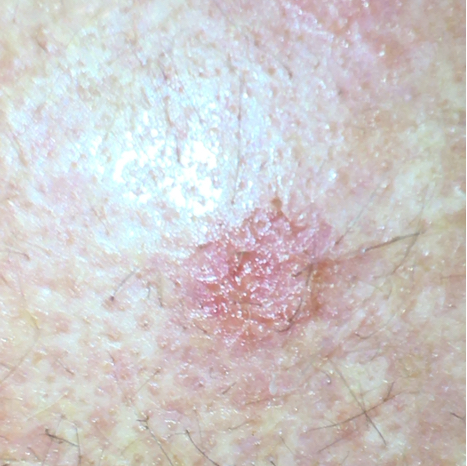

Rogowacenie słoneczne często zmienia kolor skóry na czerwonawo-brązowy z wypukłymi obszarami i szorstką, chrupiącą powierzchnią. Dzieje się tak, ponieważ dosłowne tłumaczenie rogowacenia słonecznego oznacza rogowacenie skóry wywołane przez słońce. Skorupa ma często biały kolor, ale może być również żółta lub brązowa. Plamy mają często wielkość od kilku milimetrów do centymetrów. Zwykle nie wykazują one żadnych objawów, czasami jest to uczucie niepokoju lub swędzenia. Ta nieprawidłowość skórna jest często widoczna na twarzy, grzbietach dłoni, ramionach, nogach, dekolcie, małżowinie usznej lub, u łysiejących mężczyzn, na skórze głowy. Zwykle na skórze występuje wiele AK.

Przykładowe zdjęcie rogowacenia słonecznego